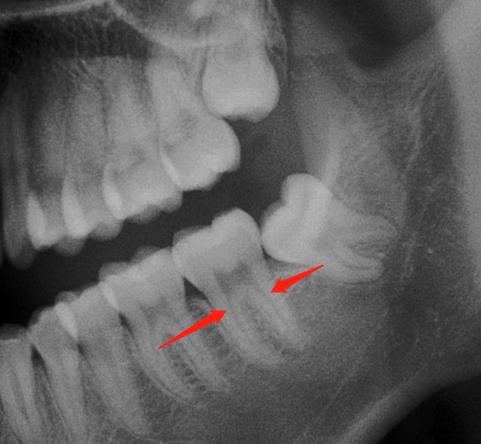

看到片子上牙根里面细细的黑色影像了没?红色箭头指的,它就是根管。根管是牙根中空的部分,里面有神经血管。